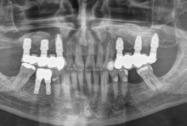

En la radiografía panorámica (Figura 5) se observan en 20 dientes los brakets viejos, en los molares 16, 27 las bandas, el canino 13 retenido en el paladar, el botón de Nance, la

ausencia de molares 26, 46. Elmolar 16 tiene un tratamiento endodóntico

En las radiografías panorámicas (Figura 11), en la comparación inicio el botón de Nance, en la final se ve sin el canino retenido, el paralelismo radicular, con la ligera perdida ósea con la que llegó la paciente en la zona antero inferior y cuadrante 4, al final continúa sin cambios.

Figura 11. Comparativa Rx Panorámica inicio final.